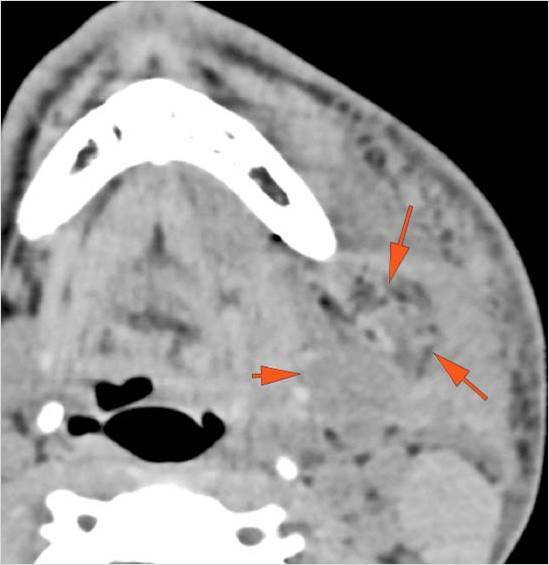

Facial and Scalp Soft Tissues and Airway

There is localized edema, hematoma or abscess within in the periauricular, other facial or scalp soft tissues, SMAS, infratemporal fossa, masticator space or oral cavity.

There is soft tissue swelling suggesting injury to the parotid or submandibular glands.